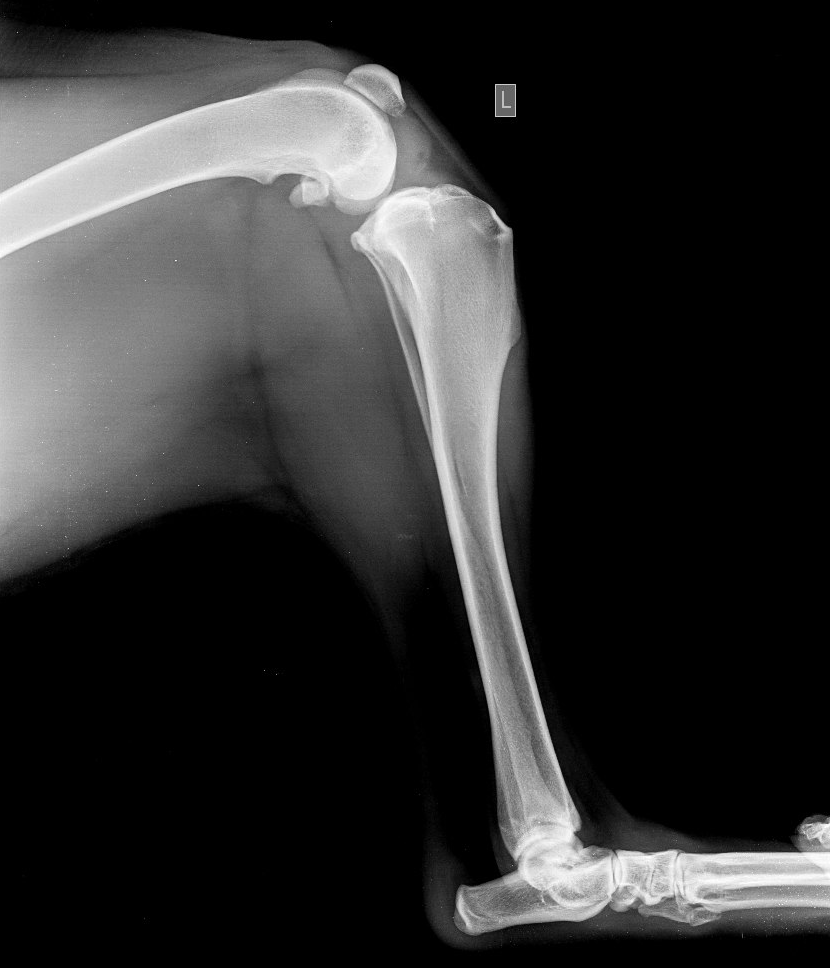

Разрыв ПКС у азиатской овчарки (хронический процесс), боковая проекция